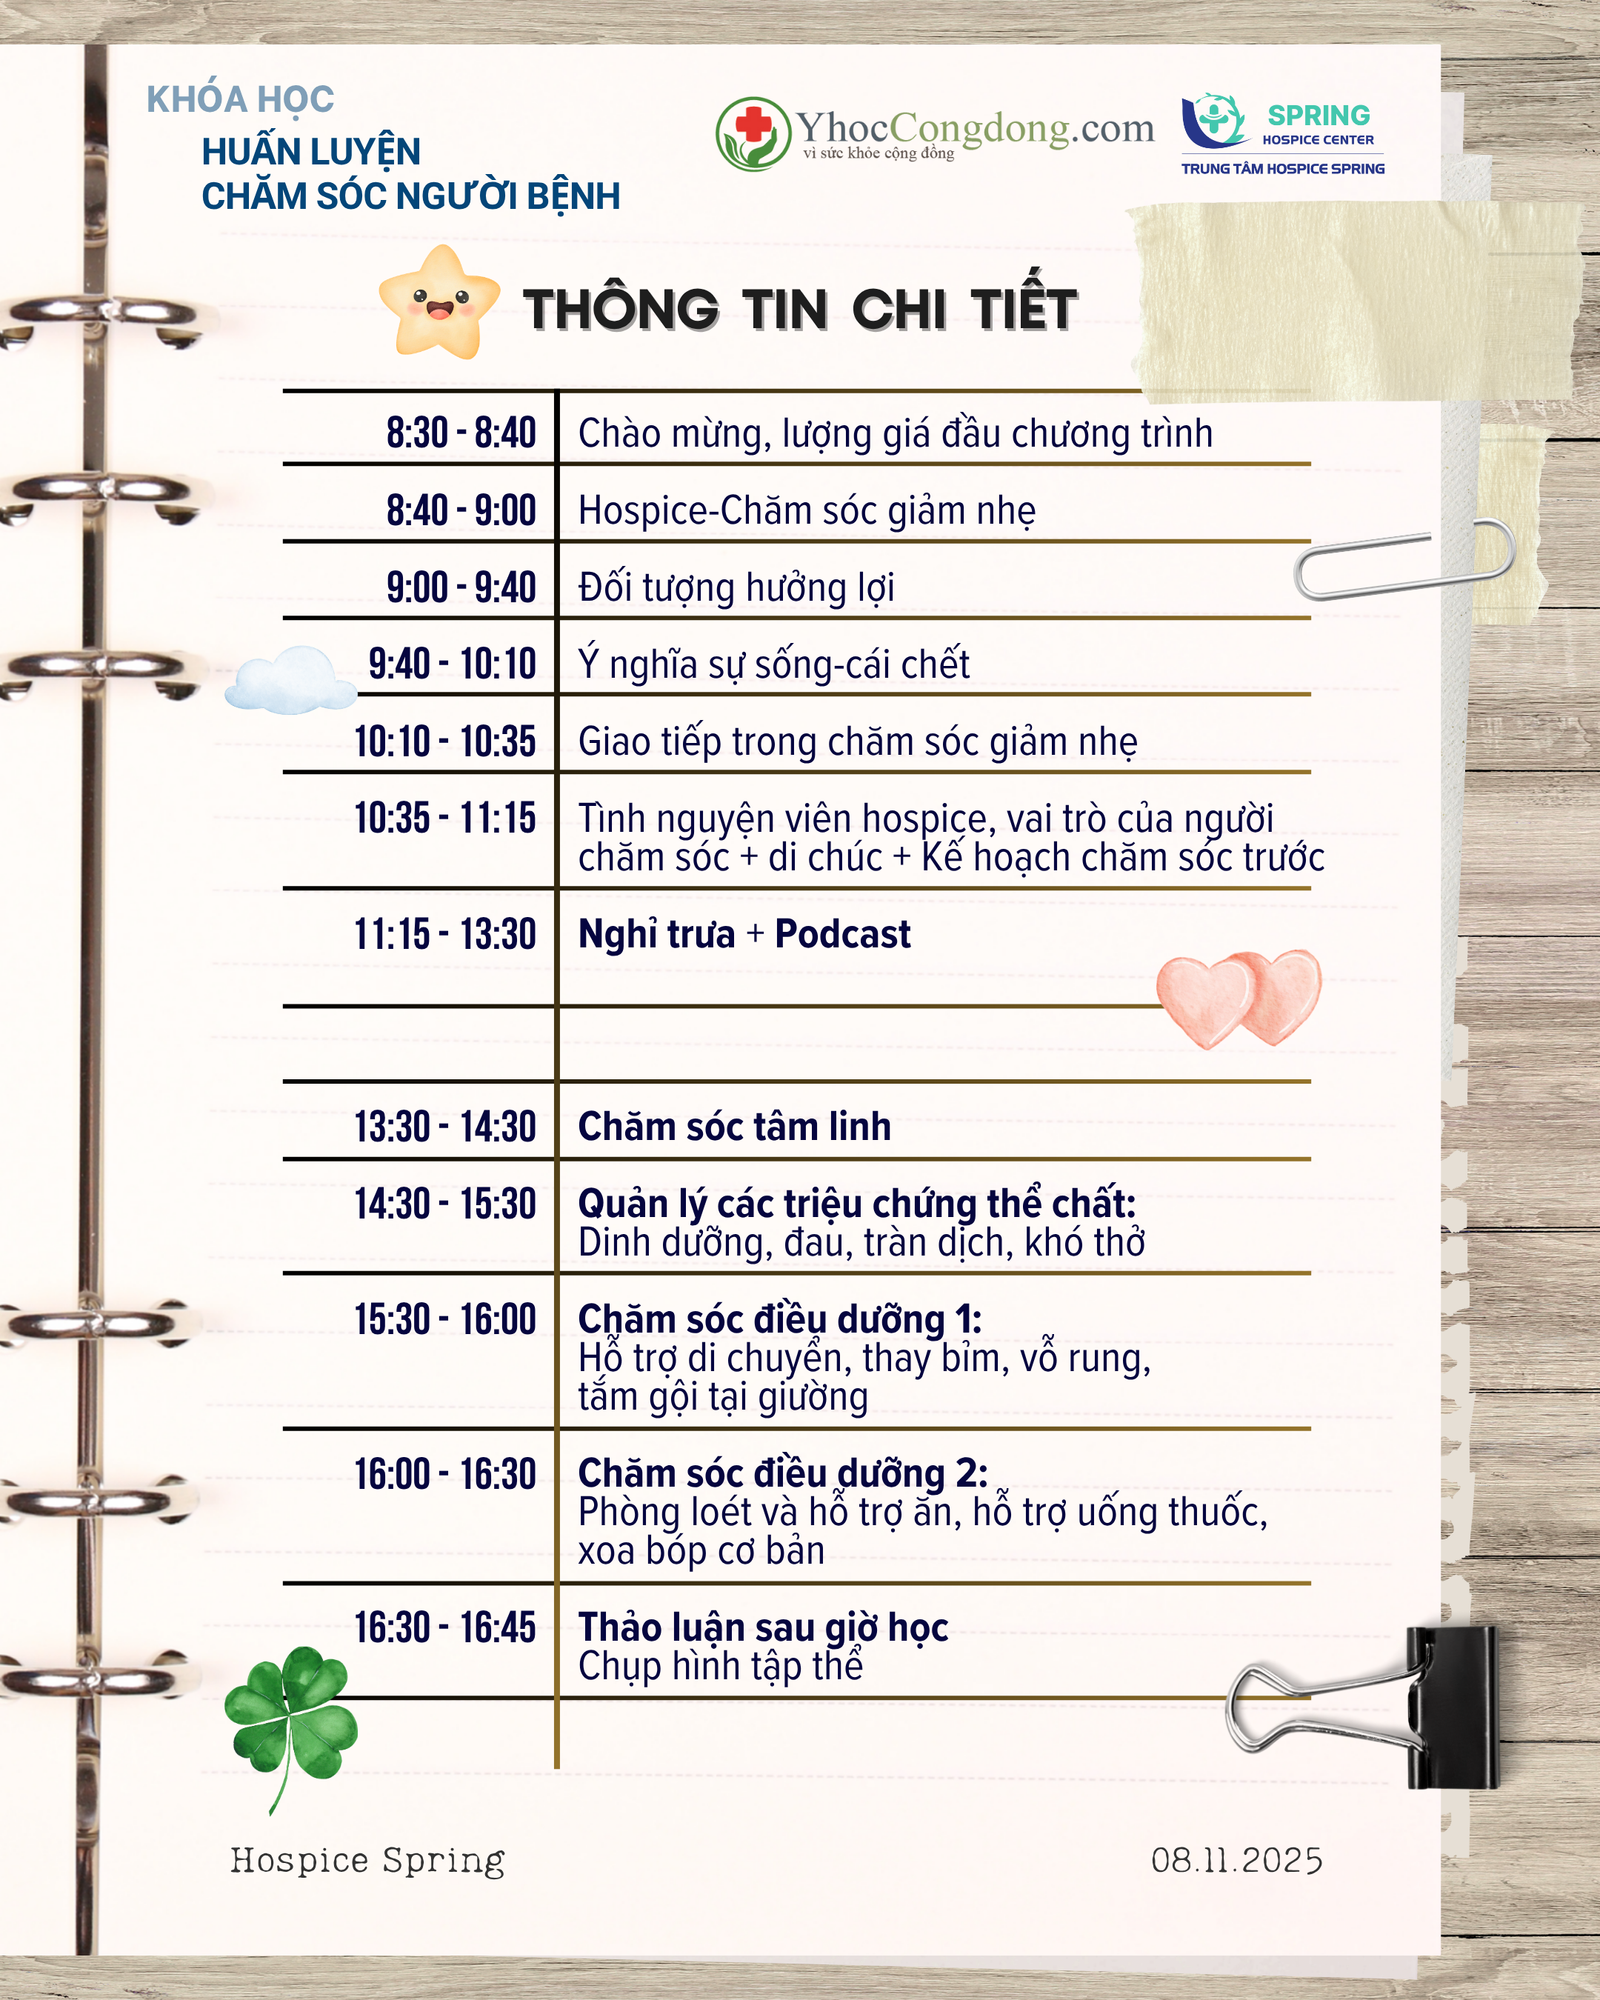

[THÔNG TIN KHÓA HỌC]

🌟 HƯỚNG DẪN CHĂM SÓC NGƯỜI BỆNH – Chăm sóc Hospice và Giảm nhẹ

✨ Khóa học được thiết kế đặc biệt cho chính bệnh nhân hoặc những người đang chăm sóc người thân bị bệnh mãn tính, bệnh ung thư giai đoạn tiến triển hoặc ở giai đoạn cuối.💚